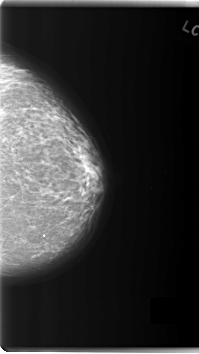

C_0183_1.LEFT_MLO

C_0183_1.LEFT_CC

LEFT_MLO LINES 5968 PIXELS_PER_LINE 3416 BITS_PER_PIXEL 12 RESOLUTION 50 NON_OVERLAY